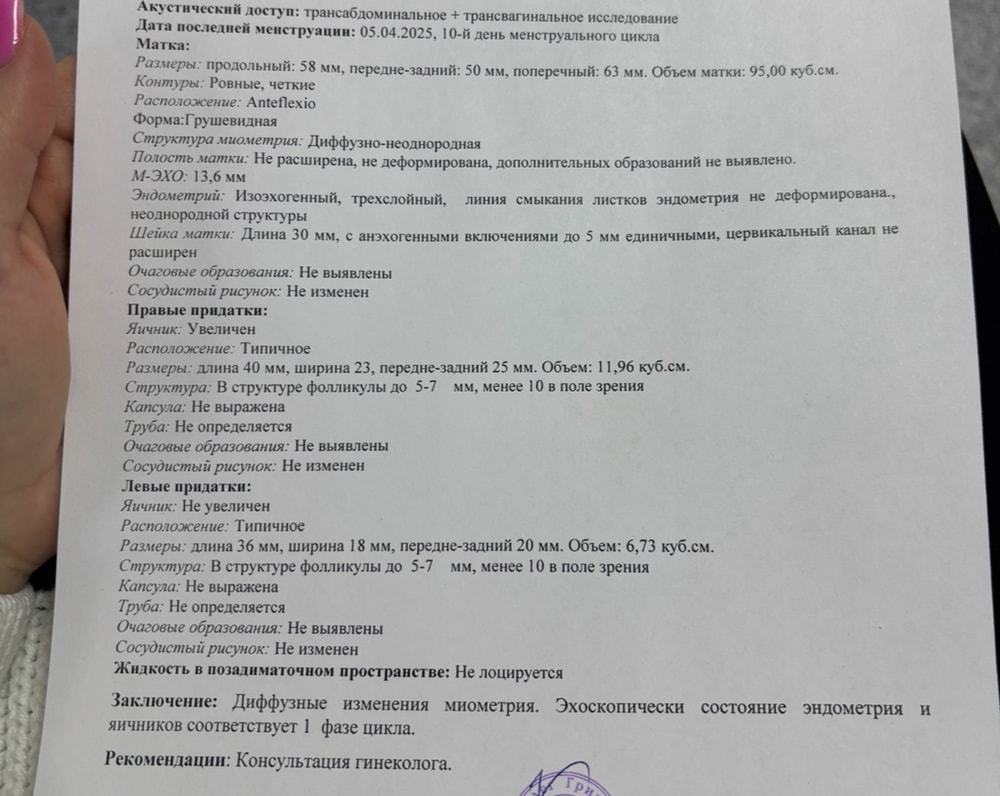

Ох не знаю с чего начать… в феврале было крио на згт, неудача. Сделала в марте гистеро выявили полип и хэ, удалили вакуумом хэ пролечила. Сейчас готовлюсь ко второму переносу на 22 апреля, очень сильно смущает эндометрий, назначили большую дозу эстрогена в итоге уже пышный 13.6 это ладно тут еще неоднородность присутствует 😩 На онлайн приеме репродуктолог сказала что ее больше смущает неоднородность но раз я пролечила хэ будем делать перенос. Остались считаные дни сижу и ломаю голову стоит ли ехать с таким эндометрием? Мне кажется тут два исхода либо меня пошлют домой и отменят перенос либо перенесут но закончится все снова неудачей 😩 девочки кто разбирается в узи? На сколько все плачевно ? Фото репродутологу забыла отправить 🤦🏼♀️ Может у кого то был похожий случай и делали перенос с неоднородным эндометрием ?